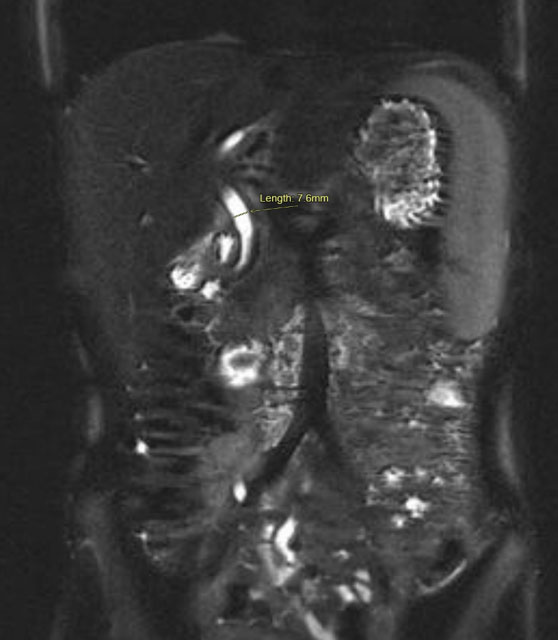

The GB was submitted to pathology for examination. Gross inspection demonstrated an intact saccular GB measuring 5.5 × 2 × 1.5 cm, without mural perforation. The GB lumen contained viscous green bile; no obstruction of the cystic duct or intraluminal calculi were seen. The GB wall was thin, without hemorrhage, significant inflammation, or edema. There was a 1.5 cm soft tan exophytic mucosal mass present within the body of the GB. Histological sections taken from the GB wall, cystic duct margin, and the mass demonstrated a complex adenomatous epithelial proliferation with a tubulopapillary growth pattern and intestinal-type differentiation. There was patchy accentuated cytologic atypia and glandular irregularity, consistent with high-grade dysplasia (Figure 3 and Figure 4). There was no evidence of stromal infiltration present to suggest invasive malignancy. The cystic duct margin was uninvolved by dysplasia. Based upon these findings, a diagnosis of ICPN with high-grade dysplasia was reported.

Figure 3: Low magnification (40×) view of hematoxylin and eosin-stained section from lesion within gallbladder wall showing variably sized and irregularly shaped glands lined by dysplastic enteric-type epithelium and containing mucinous secretions. There is no stromal desmoplasia or destructive growth to suggest invasive malignancy.